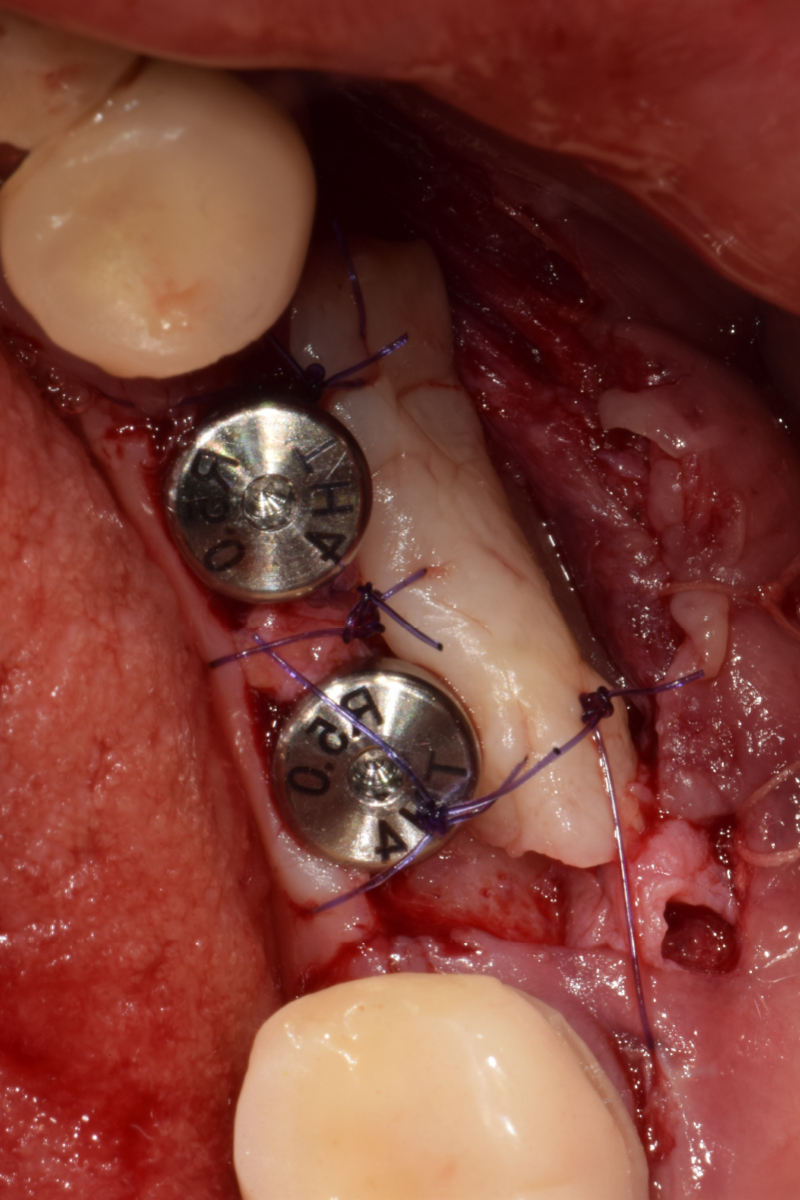

임플란트 픽스쳐 식립 (개당 10분 소요)

잇몸 뼈 이식 / 보철물 제작

즉시 식립 임플란트 전후 사례

식립 후